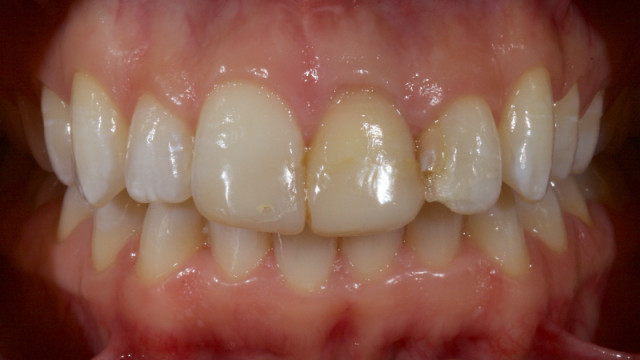

Technique for ‘Cementing’ and Retaining Conservative Ceramic Onlay Provisionals